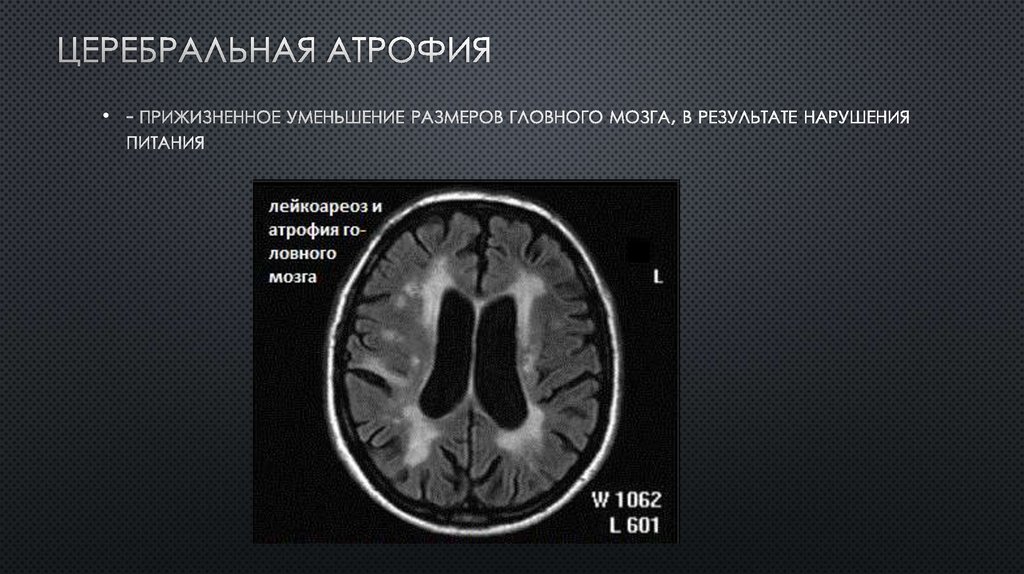

Хроническая ишемия головного мозга и лейкоареоз: симптомы и лечение